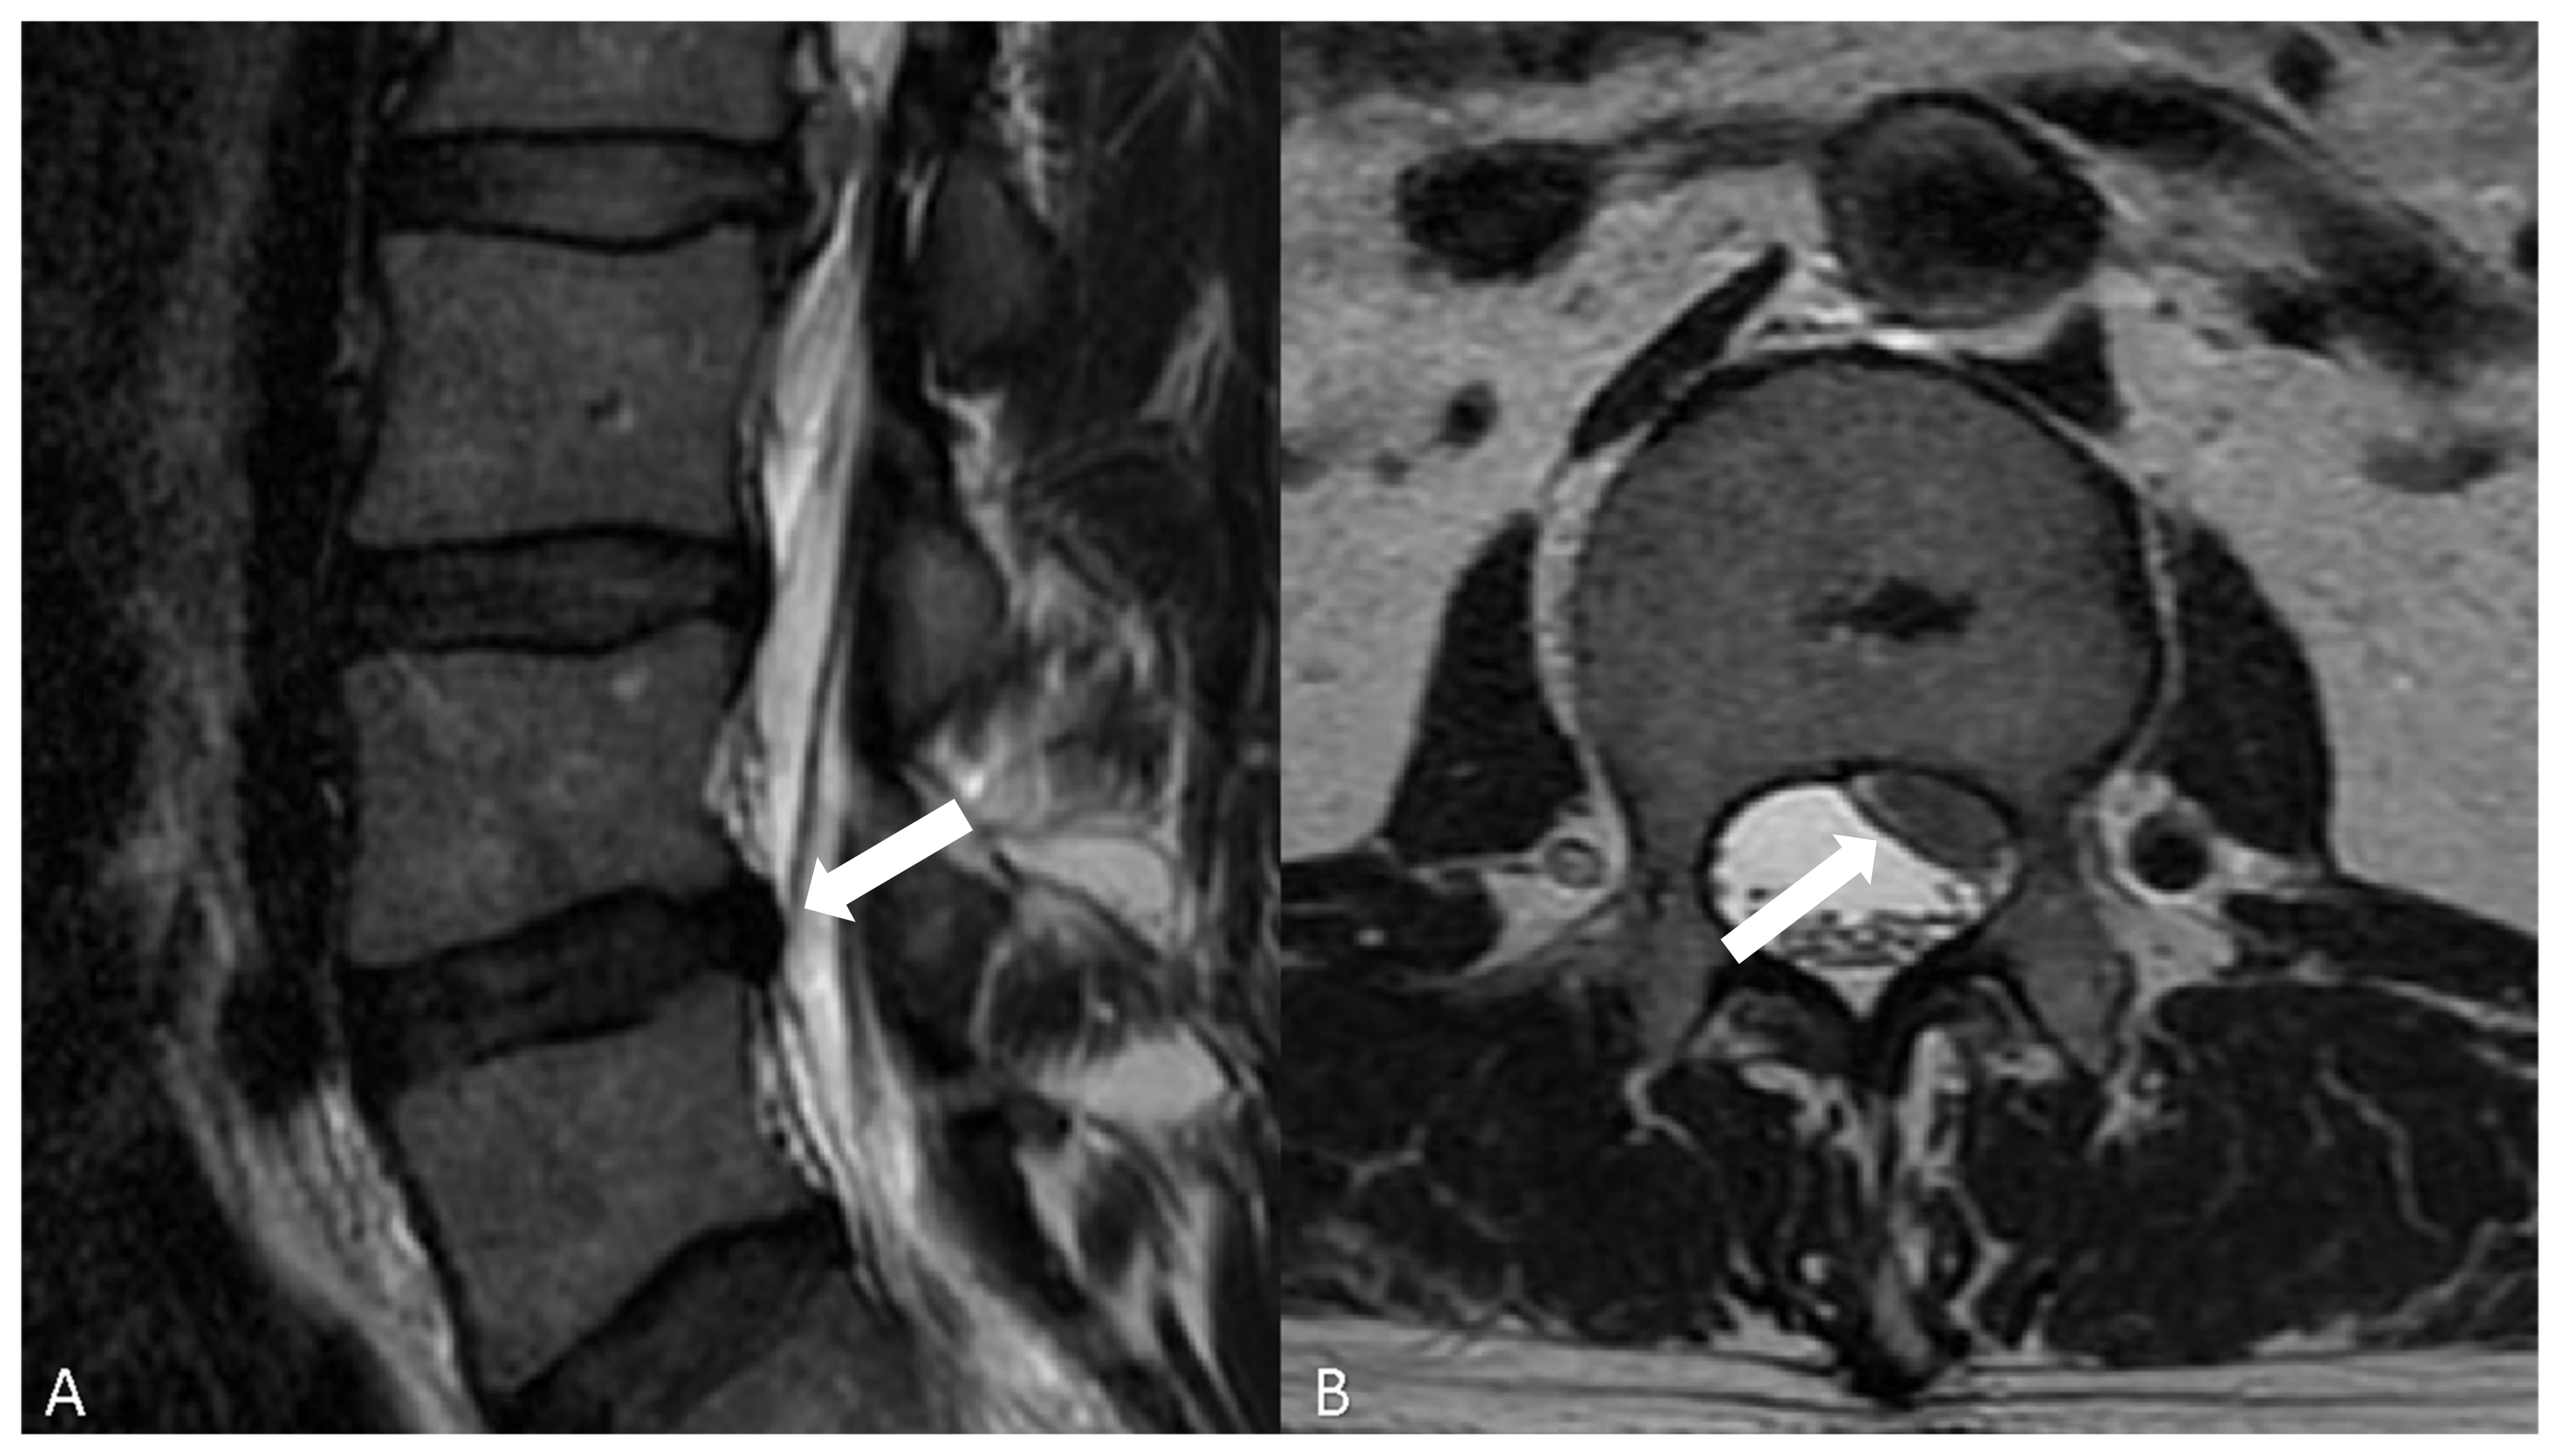

Before MR imaging, the “gold standard” imaging modality to visualize spinal disc was the discography, which consists of the puncture of the intervertebral disc with a needle under fluoroscopy and successive injection of contrast agent [41]. Nowadays, MR is the gold standard for assessing the disc structure [42,43] and should be performed as the first examination. The most commonly used protocol for detection of degenerative disease of the spine includes sagittal T1- and T2-weighted images and sagittal short tau inversion recovery (STIR). The latter sequence helps in the characterization of edema of the medullary bone [44]. Axial T2-weighted images acquisitions are frequently performed on lumbar disc levels to detect potential foraminal or extraforaminal disc herniation (Figure 3).

Figure 3.

(A) T2-w, sagittal plan, showing multiple lumbar disc herniations, the most important at the level L3–L4 (white arrow); (B): T2-w, axial plan, showing a lumbar disc herniation, posterior, involving the left side of the spinal canal with compression of some nerves (white arrows).

Axial T2-Weighted images also help to identify the accurate relationship between the disc bulging (or herniation) and surrounding nerve roots and spinal cord. T2-Weighted sequences are very useful for characterizing the structure of lumbar intervertebral discs. For cervical spine exploration, a 3-dimensional gradient echo sequence provides a slice thickness of less than 1 mm, helping to see more precisely the intervertebral foramina and the nerve roots [41]. The administration of contrast agent should be reserved to well-selected patients, even if it can be very useful to study bone, intra-articular and muscular findings. Even though minimal signs of spondylolisthesis are noted in a standard supine MR, as, for example, excessive fluid in facet joints, bone instability must be suspected and a dynamic orthostatic X-ray or an orthostatic MR, if it is available, must be suggested to the patient. Specifically, the upright MR can be a supplementary diagnostic examination when there are negative results in conventional MR in symptomatic patients or when surgery is scheduled [45].